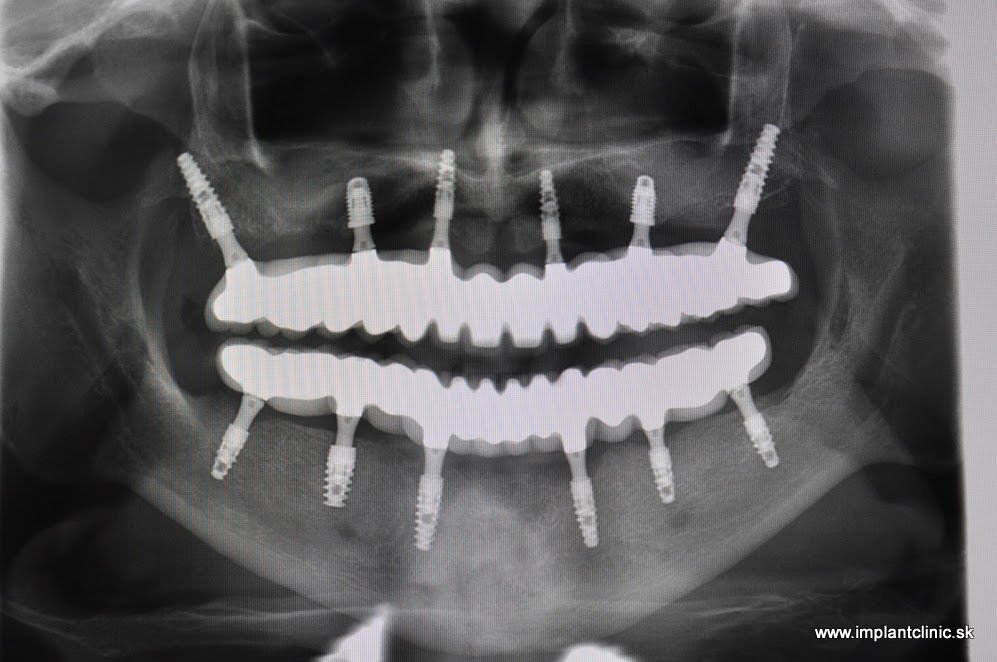

Konečný snímok po nasadení hotových mostíkov

Snímka po zavedení zubných implantátov a nasadení dočasného mostíka